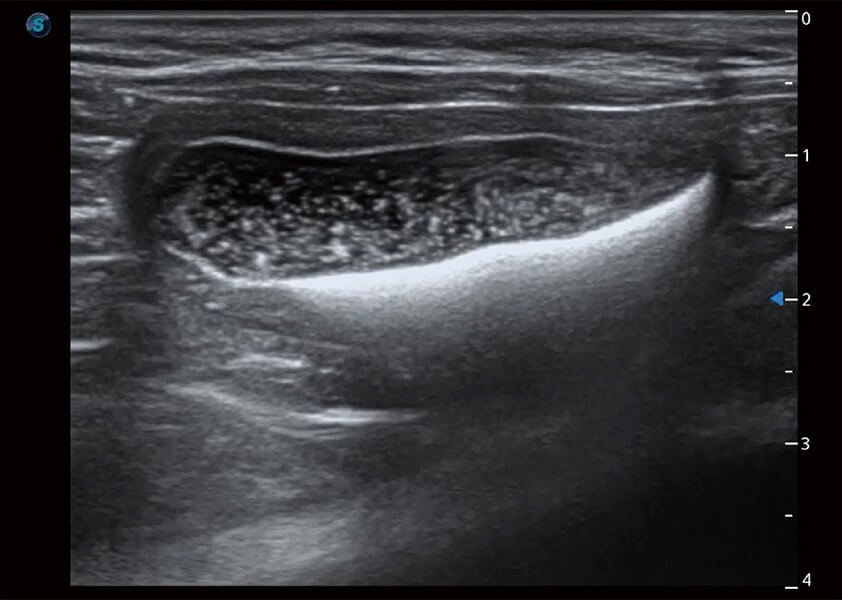

ProPet 60 作為一款高端臺式動物超聲設備,為動物醫(yī)生的日常診斷提供了一系列貼合動物臨床需求、解決臨床實際問題的高級成像功能。憑借全系列高清探頭,滿足醫(yī)生對腹部、心臟、生殖、淺表、肌骨等成像的所有需求,切實幫助您提升檢查效率,提高診斷信心。

動物是人類最親密的朋友和最值得信賴的伙伴。開立醫(yī)療也一直致力于探索動物專用的超聲影像解決方案。 全新推出的ProPet系列,是開立在動物超聲影像智能化、專業(yè)化、精準化的一次跨越式革新。動物不能用言語來表述自己的不適,通過超聲影像,ProPet系列搭建了動物醫(yī)生與不同物種溝通的“橋梁”,為動物醫(yī)生注入了“治愈之力”。